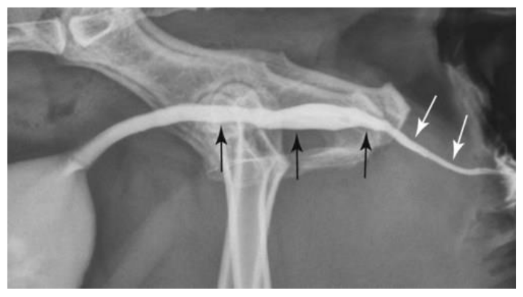

Através da Uretrocistografia Retrógrada foi visualizado um ponto de extravasamento de contraste para a cavidade abdominal advindo de uretra prostática, porém ainda havendo repleção da vesícula urinária pelo contraste, o que indicava que havia uma ruptura uretral, mas que esta seria parcial.

Após aproximadamente 15 dias em que o paciente permaneceu com catéter uretral fixado, foi realizado um novo exame radiográfico contrastado, em que os achados foram similares ao primeiro realizado, observando ainda a presença de um ponto de extravasamento de contraste em topografia de uretra prostática.

Após os 7 dias, foi realizada a última radiografia contrastada, que não evidenciou sinais de extravasamento de contraste e confirmou a cicatrização do ponto de ruptura.

O prognóstico em casos semelhantes está diretamente associado à precocidade do diagnóstico, à extensão da lesão e à técnica cirúrgica empregada (NYLAND; MATTOON, 2014). Neste trabalho, a utilização de exames de imagem, especialmente a uretrocistografia retrógrada, foi fundamental para a confirmação diagnóstica, corroborando a literatura que reconhece este exame como padrão-ouro para a avaliação de rupturas uretrais (CÔTÉ, 2002).